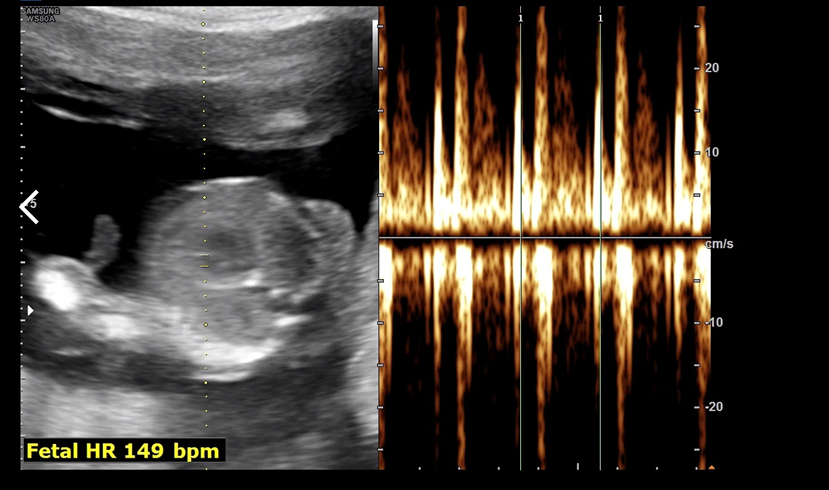

탯줄을 통해 아기에게 영양분이 잘 오고 가는지 뭐 그런 걸 체크하셨던 거 같다.

심박수도 점점 안정화되어 149 bpm까지 내려왔다.